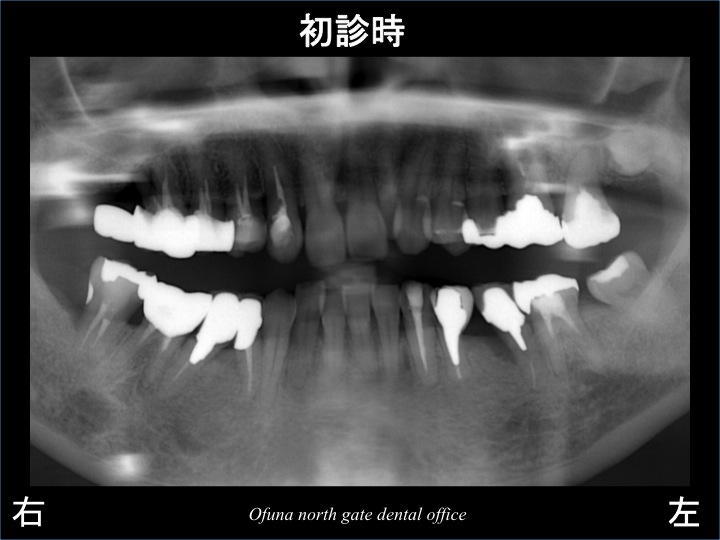

以下のレントゲン写真が初診時になります。

神経のない歯が非常に多いのです。

以下のレントゲン写真の青丸は、神経がない歯です。